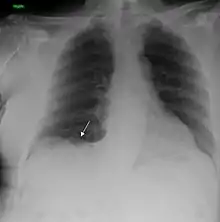

Performing a chest radiograph is one of the first investigative steps if a person reports symptoms that may be suggestive of lung cancer. This may reveal an obvious mass, the widening of the mediastinum (suggestive of spread to lymph nodes there), atelectasis (lung collapse), consolidation (pneumonia), or pleural effusion.[7] CT imaging of the chest may reveal a spiculated mass which is highly suggestive of lung cancer, and is also used to provide more information about the type and extent of disease. Bronchoscopic or CT-guided biopsy is often used to sample the tumor for histopathology.[17]

Lung cancer often appears as a solitary pulmonary nodule on a chest radiograph. However, the differential diagnosis is wide. Many other diseases can also give this appearance, including metastatic cancer, hamartomas, and infectious granulomas caused by tuberculosis, histoplasmosis or coccidioidomycosis.[66] Lung cancer can also be an incidental finding, as a solitary pulmonary nodule on a chest radiograph or CT scan done for an unrelated reason.[67] The definitive diagnosis of lung cancer is based on the histological examination of the suspicious tissue[1] in the context of the clinical and radiological features.[6]